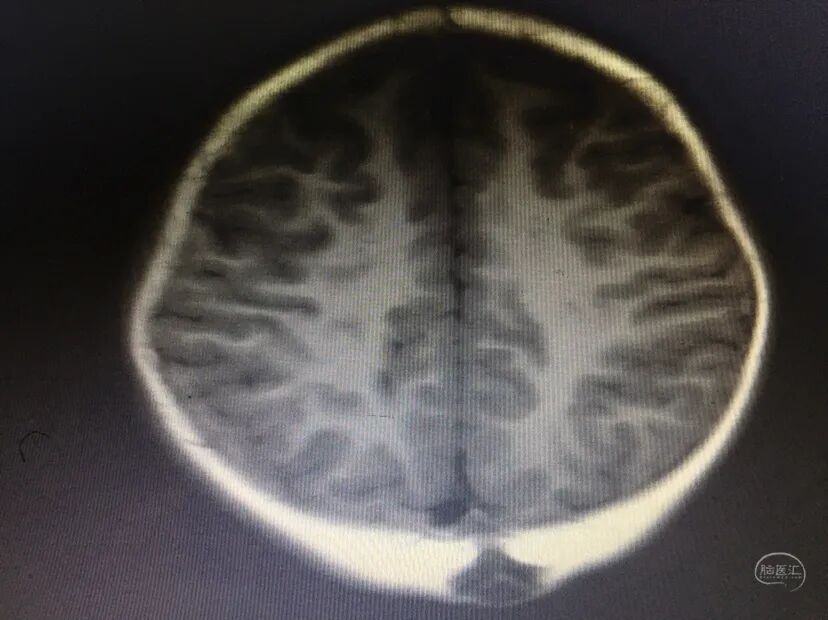

术后情况

术后伤口愈合可,无皮下积液。